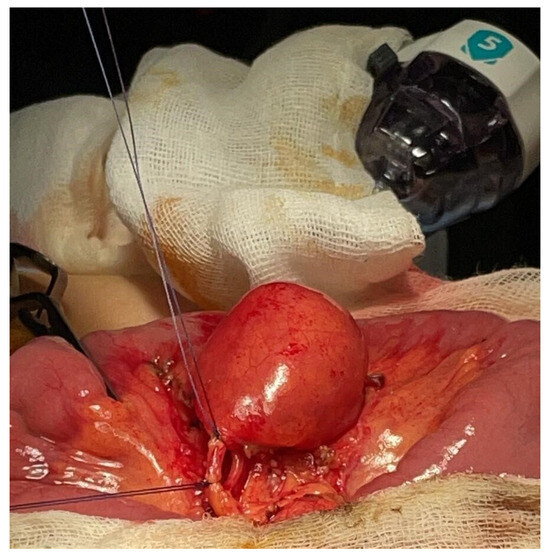

Figure 2.

Case 1—Intraoperative appearance of MMD.

A 6-year-old boy with no prior medical history presented to a peripheral hospital’s emergency department with periumbilical pain and rectal bleeding. His vital signs were as follows: a temperature of 36.6 °C, a pulse rate of 107/min, a blood pressure of 116/75 mmHg, and a respiratory rate of 28/min. Laboratory tests indicated an Hb of 6.9 g/dL (normal values for age > 11.5 g/d), while the serum leukocyte count and C-reactive protein (CRP) were within normal ranges. A blood transfusion was administered, stabilizing his condition temporarily. Abdominal US showed no pathological findings. Subsequent upper and lower endoscopic evaluation revealed residual blood in the colon and ileum, but no active bleeding sites. The patient was then transferred to our center where repeated abdominal US revealed a cystic lesion in the mesogastric region, approximately 2 cm in length and communicating with the small bowel lumen (Figure 1). A bleeding MD was then suspected, and the patient underwent laparoscopic exploration. The entire small bowel was examined, and a mesenteric mass similar to an intestinal duplication was found, approximately 60 cm from the ileocecal valve. The lesion was exteriorized through the umbilical incision (Figure 2). Dissection confirmed that the mass was connected to the mesenteric side of the small bowel, with a short artery arising from a mesenteric branch, confirming the diagnosis of MMD (Figure 3). A 5 cm long segment of the small bowel including the mass was resected, and a primary end-to-end anastomosis was performed. The postoperative course was uneventful, and the patient was discharged after five days with no need for further blood transfusions. Histopathological evaluation confirmed the diagnosis of MMD with ectopic gastric mucosa. Inizio modulo